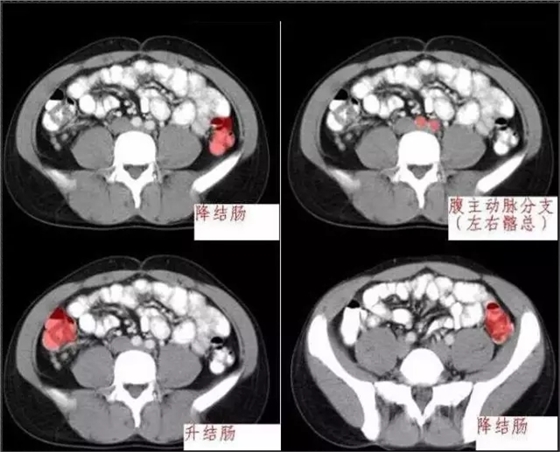

640.webp (3).jpg